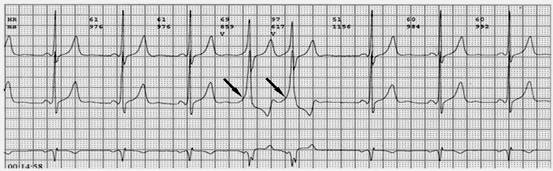

2.心电图表现:典型预激表现为窦性搏动的PR间期<0.12秒,某些导联的QRS波时限>0.12秒,QRS波起始部粗钝(称delta波),ST段有继发改变,T波与主波相反。